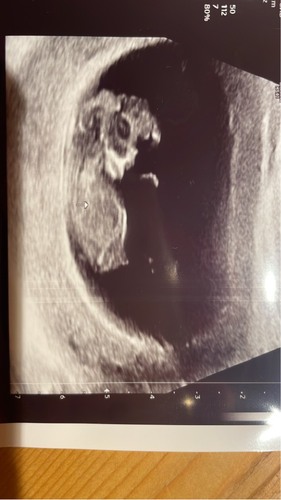

12+1, weet niet of de echo duidelijk genoeg is we kregen alleen deze mee vandaag! Kan iemand hier al wat uithalen toevallig? 🙈

Heb je nog meer foto’s? Volgens mij is de nub niet te zien op deze echo